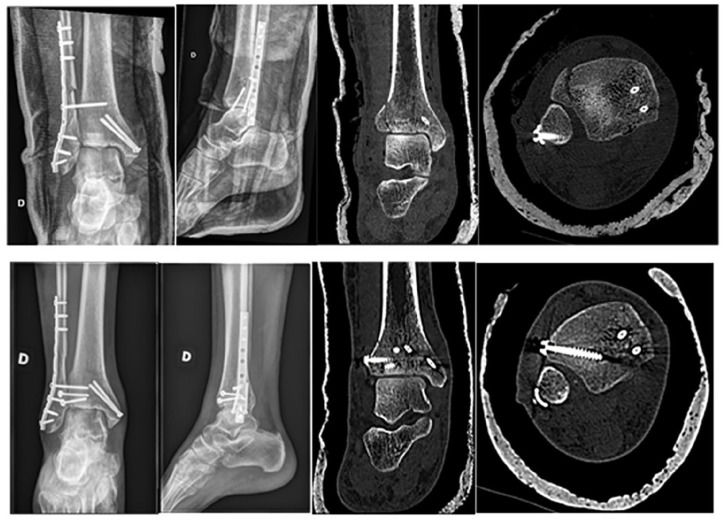

Background: Tillaux-Chaput tubercle fractures in adults often go unnoticed on standard radiographs in the setting of other malleolar fractures. This study aimed to identify clinical and radiologic factors associated with these fractures to develop a decision aid for computed tomographic (CT) diagnosis.

Results: Tillaux-Chaput fractures were undetected on standard radiographs in 60% of cases. In multivariate analysis, only age >60 years and injury mechanisms with Lauge-Hansen pronation-external rotation stage III or IV injuries were found to be highly associated with Tillaux-Chaput tubercle fractures.

Conclusion: We recommend routine CT scan evaluation for patients >60 years old with stage III or IV pronation-external rotation ankle fractures.

Abstract Image